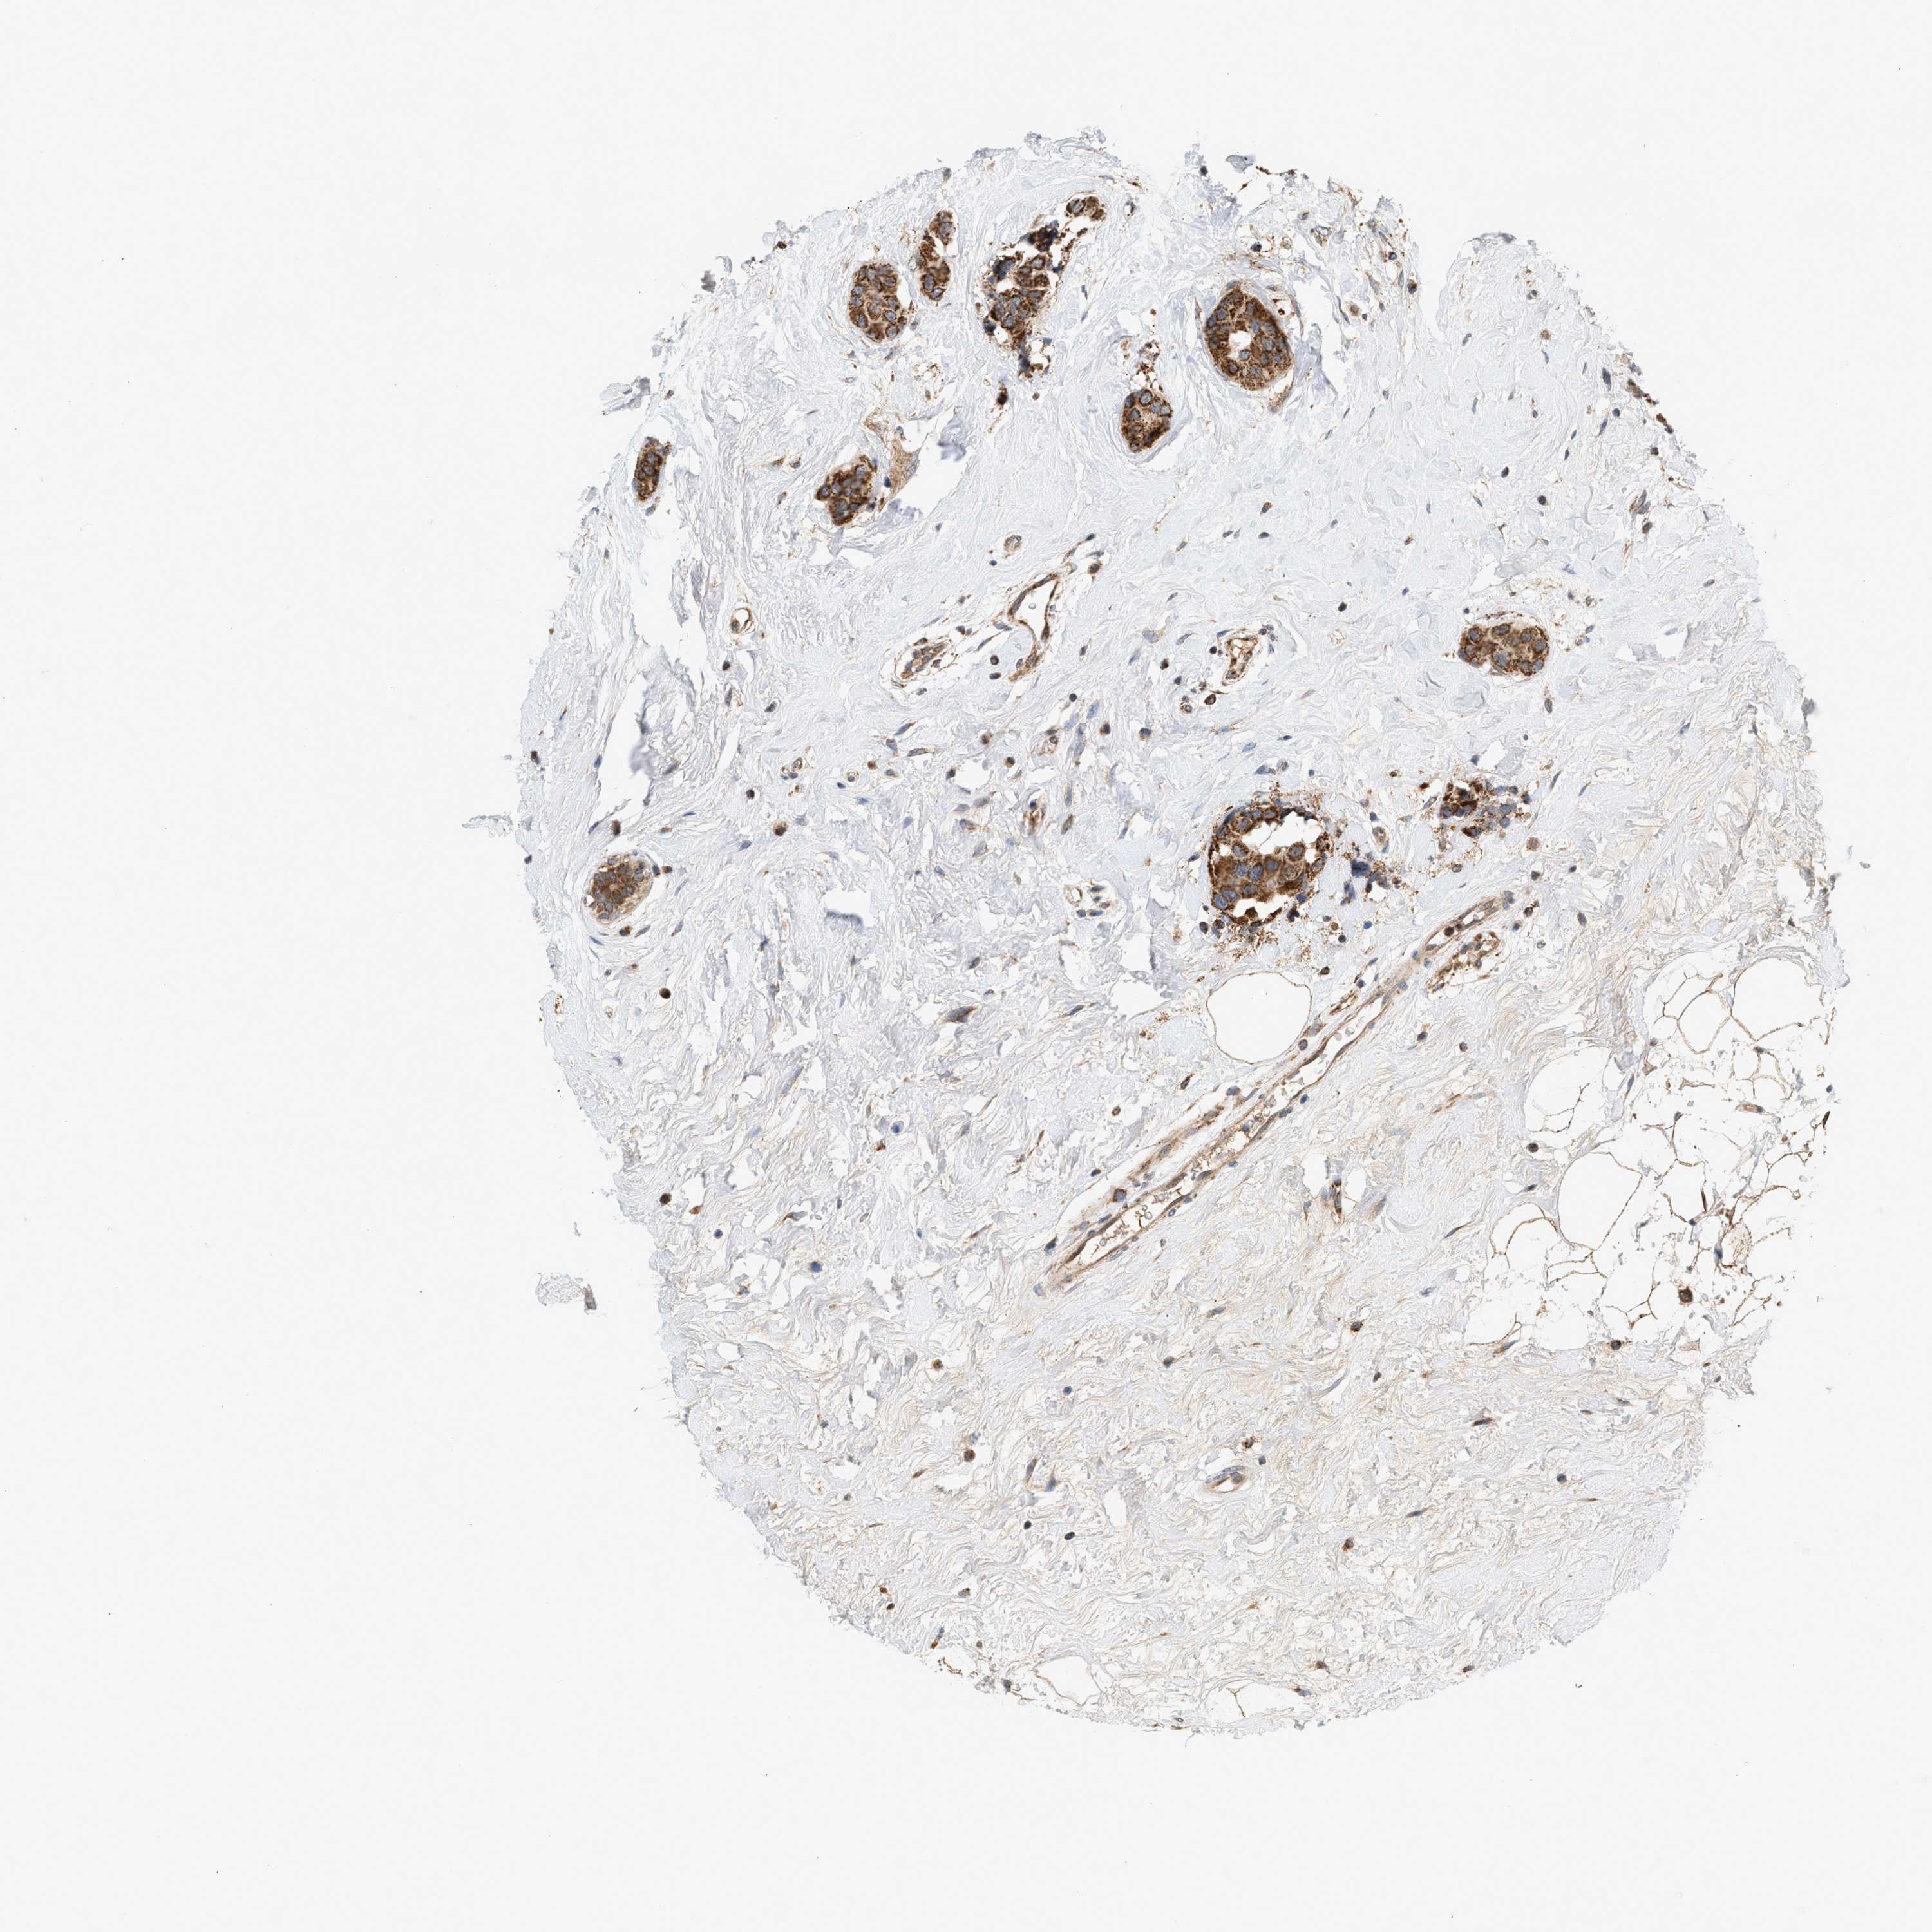

CANCER BREAST CANCER Show tissue menu

BRCA TCGA BRCA VALIDATION PROTEIN EXPRESSION